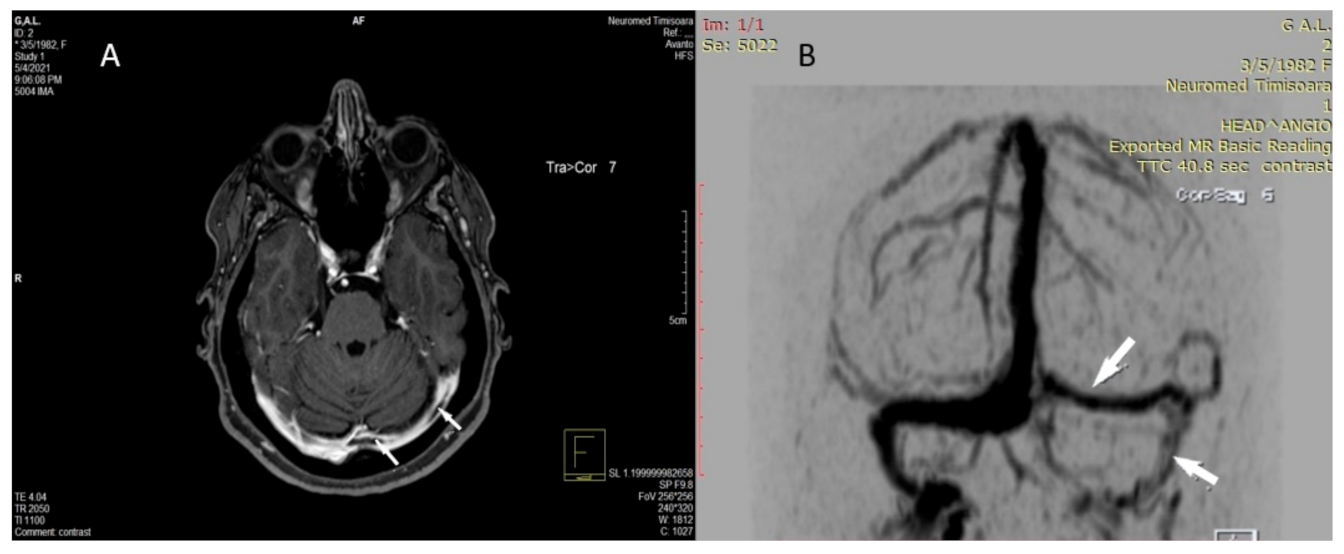

2.2. Imaging